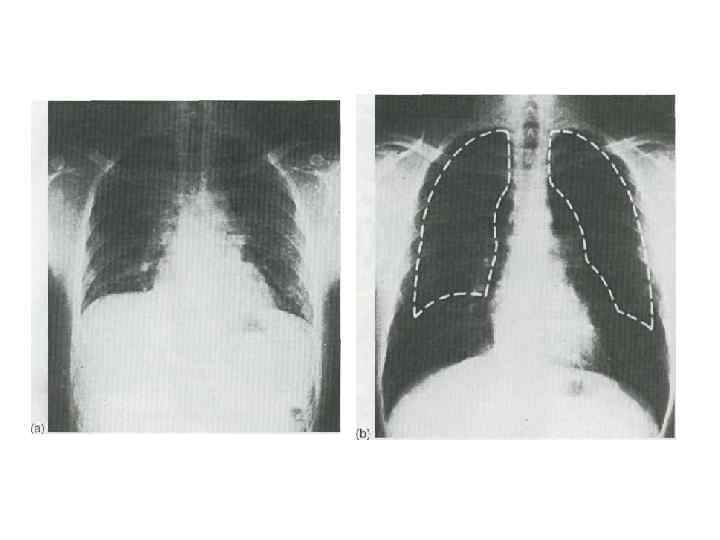

Изменение объема грудной клетки во время вдоха и выдоха Увеличение объема грудной клетки в переднезаднем и вертикальном направлениях. Увеличение в боковом направлении. Ребернодиафрагмальные синусы открыты 1. Сокращение диафрагмы. расслабление 2. Наружные межреберные мышцы сокращены. 3. Внутренние межреберные мышцы расслаблены.